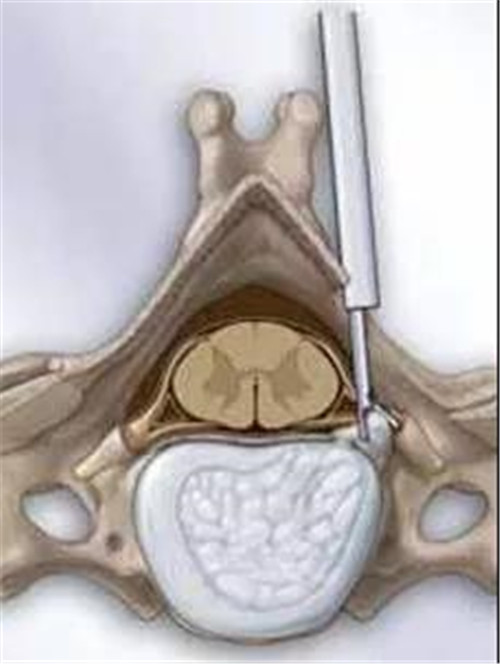

为了降低患者对手术的恐惧心理,管床医生焦伟东医师耐心地讲解关于手术的益处,“颈椎椎间孔镜(key-hole)手术非常适合像您这样单侧神经根症状的外侧型颈椎间盘突出患者,跟其他类型的手术相比有很多优点:切口小、出血少,恢复快、住院时间短,活动度不受影响,最重要的是效果好费用又低。”

技术示意图(左)和术后复查三维CT

由于入院后的检查显示血糖指数过高,经过几天的休养陈大爷将血糖调到了正常值。9月7号,潘磊主任医师主刀、王诗成副主任医师、焦伟东医师协助为他实施了微创手术,一个小时后,成功将压迫神经的部分取出,手术顺利完成。“刚做完手术就感觉手已经不麻了!”,第二天下午,陈大爷已经可以下地走动。